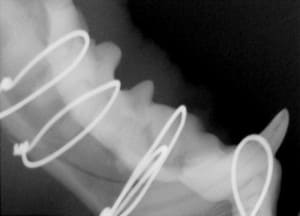

Crowns

Crowns are placed on fractured teeth to provide the strength to the tooth structure. This is often performed on working dogs or pets who need their teeth for specific activities. The crowns are made of non-precious metal and require one episode of anesthesia to prepare the tooth and create the molds for crown fabrication, and a second anesthetic episode to fit and cement the crowns.